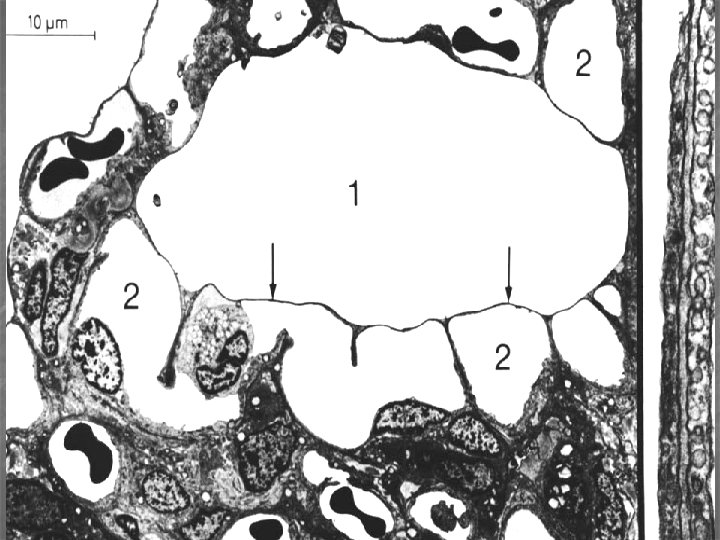

Plicní alveolus (300 – 500 mil. v každé plíci, plocha 70 – 80 m 2) n n n respirační epitel (2 typy pneumocytů: membranózní* - 97% plochy, výměna plynů, granulovaný** – 3% plochy, plicní surfaktant retikuloelastická membrána (vlákna, fibroblasty, amorfní substance) krevní kapiláry – souvislé Póry v interalveol. septu – kolat. cirkulace vzduchu alveolární makrofágy * alveolární buňky I, ** alveolární buňky II

bronchiolus alveolus Interalveolar septum macrophages

Krev-vzduch bariéra (šířka 0, 1 – 1, 5 μm) n n n surfaktant cytoplazma membranózního pneumocytu lamina basalis respiračního ep. lamina basalis endotelu kapiláry cytoplazma endotelové buňky

Respirační epitel a bariera vzduch-krev lumen kapiláry s erytrocyty Vazivo Membranózní pneumocyt Granulózní pneumocyt

Blood-air barrier